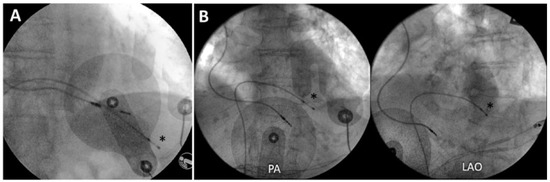

Familial hypercholesterolaemia: increasing physicians’ awareness in order to prevent early death. Familial hypercholesterolaemia (FH) is one of the most frequent autosomal dominant genetic conditions (1/200–300) and is still underdiagnosed and undert...